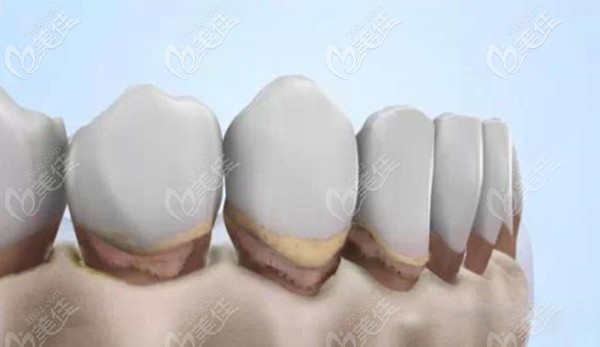

今天,給大家講解一下“全瓷牙特便宜的多少錢一個(gè),用這種價(jià)格的裝一口全瓷牙的話需要多少錢?”... b1357 G0 V0